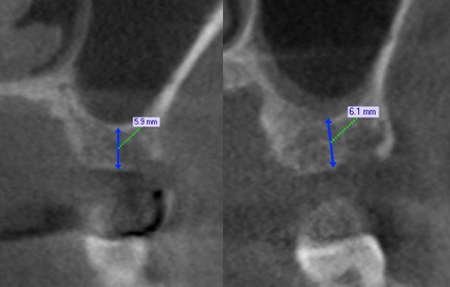

→ 26번 치아 CT

상악 좌측 구치부 안에 뼈가 부족한 검은 자리가 보이지만 수술 하면서 염증을 제거하고 인공뼈를 이식한다면 좋은 결과가 있을 것으로 예상되었습니다.